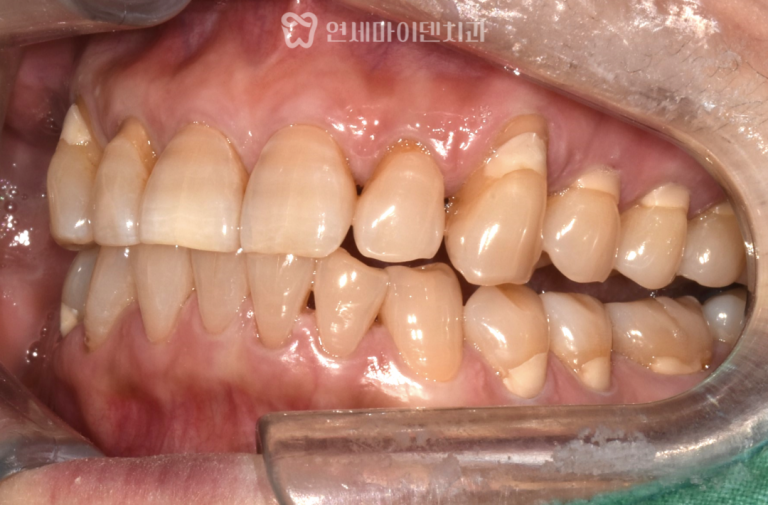

환자분은 전반적인 치아 상태는 매우 튼튼했지만,

잇몸 염증으로 인해 치조골까지 녹아버려서

타치과에서 발치 진단을 받으셨지만

치아를 살리기 위해 저희 병원에 오셨습니다.

잇몸 패임으로 신경 괴사된 치아

환자분은 처음에는 가벼운 잇몸 시림 증상만 느끼셨다고 합니다.

통증이 심하지 않아서 따로 치료를 받지 않으셨지만

이후 잇몸 여드름처럼 고름이 생겨서

치과를 찾아가셨다고 합니다.

저희 병원에 오시기 전, 다른 치과에서 진단받은 결과는

잇몸이 패이면서 염증이 심해졌고 치아 뿌리 주변의 뼈가 녹아서

결국 발치를 해야 한다는 소견이었습니다.

초진 당시 구강 내부를 살펴보니

치아와 잇몸의 경계 부위가 깊게 패인

‘치경부 마모증‘이 심하게 진행된 상태였습니다.

또, 잇몸 여러 부위에서 여드름과 같이

고름이 차있는 모습도 확인할 수 있었습니다

잇몸이 지속적으로 패이면서 치아의 목 부위가

도끼로 찍힌 것처럼 손상되었고,

그로 인해 치수 신경이 괴사되어 있었던 상황입니다.